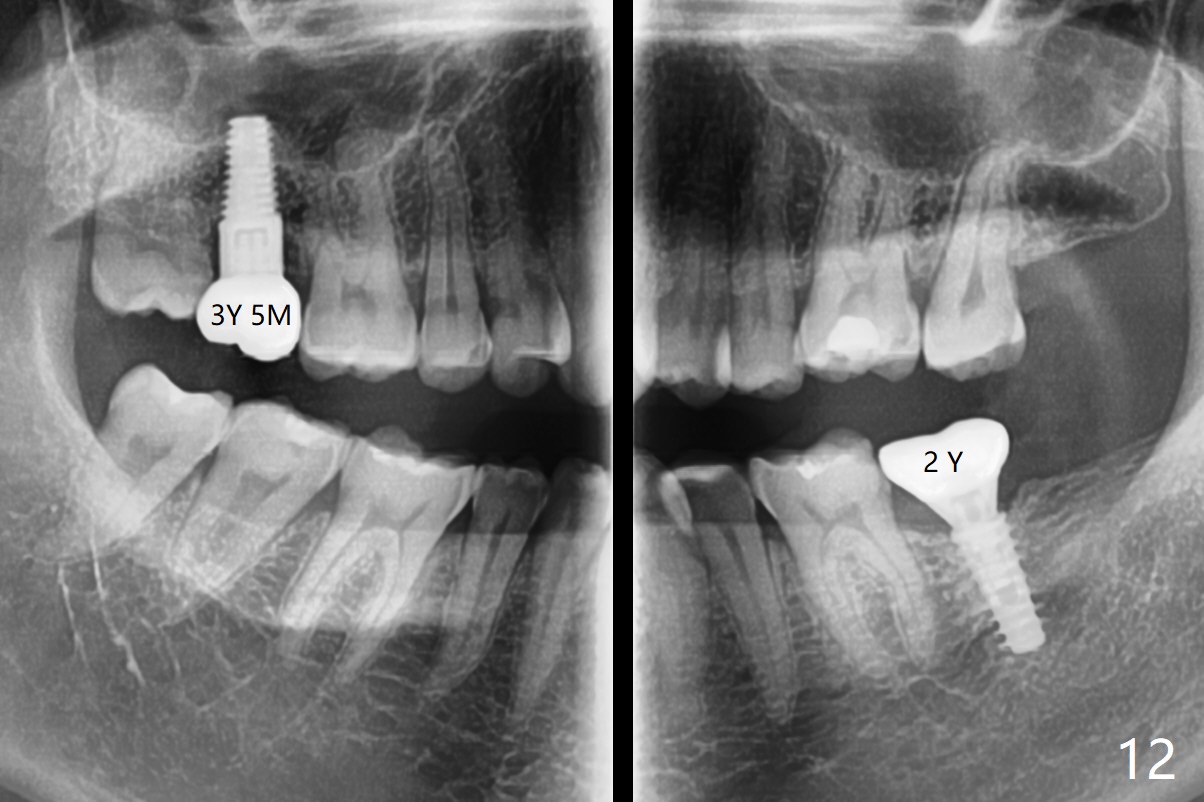

Mastication pain at #18 persists 2 years post cementation (Fig.12).  Occlusion is adjusted next.  The implant at #2 has functioned 3 years 5 months.